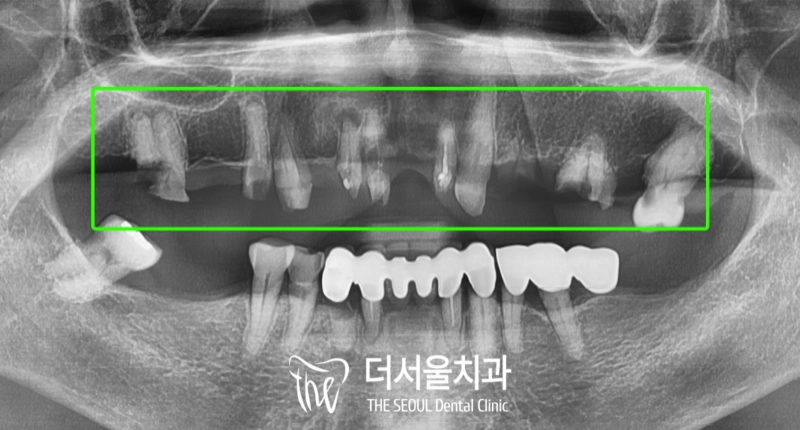

환자의 구강 상태를 확인한 결과,

다수의 잔존 치근들이 눈에 띕니다.

심한 충치로 인해 검게 썩어 있는 파절 부위를

확인할 수 있었는데요.

이와 더불어, 심한 치주 질환까지 동반되어

나타나 있는 상태였습니다.

알고 보니,

예전에 야매로 했던 치아가 빠졌다네요..

전체를 통으로 묶어서 했던 것이

충치로 인해 썩어버렸기 때문에

이렇게 잔존 치근만 남아있게 된 것입니다.

『즉시식립 임플란트 증례』

더서울에서 항상 했던 그대로

디지털 분석을 통해 인접치,

주변 조직과의 위치 관계를 파악했습니다.

전과는 달리 잔존 치근이 사라지고

튼튼하고 심미적인 지르코니아 보철이 올라가 있네요.